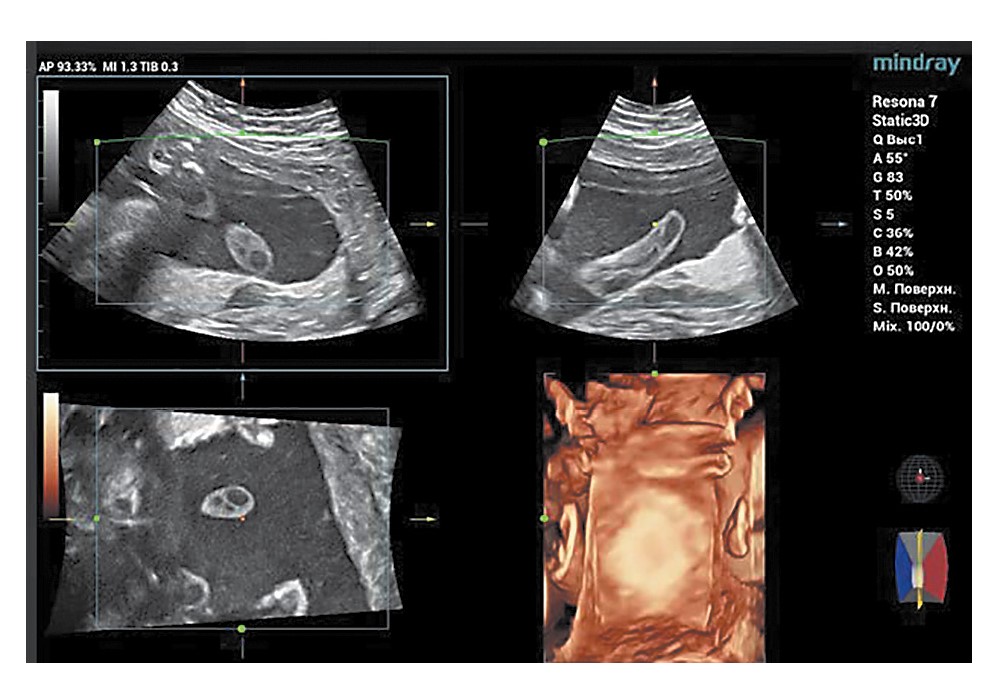

При исследовании последов основной группы признаки гнойного хориоамнионита (ХА) выявлены в 30 (55,6%) наблюдениях, виллузит сосудов хориальной площадки – в 25 (46,3%) случаях, фунизит – в 12 (22,2%) наблюдениях, острый диффузный базальный децидуит – в 26 (48,1%) наблюдениях (рис. 4). В контрольной группе указанных изменений не выявлено.

Рис. 4. Продуктивный виллузит. ×200.

Fig. 4. Productive villusitis, ×200.

В основной группе в 23 (42,6%) наблюдениях установлено соответствие строения ворсинчатого дерева сроку беременности. Ускоренное созревание ворсинчатого дерева отмечено в 12 (22,2%), а отставание – в 19 (35,2%) наблюдениях, при этом в структуре ворсинчатого дерева преобладали незрелые промежуточные ворсины. В 18 (33,3%) выявлены мелкие и крупные инфаркты ворсинчатого дерева, а в 9 (16,7%) обнаружены крупные субхориальные тромбы, а также многочисленные скопления склерозированных ворсин и некрозы базальной пластинки. Признаки хронической маточно-плацентарной гипоксии (многочисленные мелкие терминальные ворсины с множеством синцитиальных почек) обнаружены в 22 (40,7%) наблюдениях. В контрольной группе в 45 (93,8%) наблюдениях установлено соответствие строения ворсинчатого дерева сроку беременности и в 3 (6,3%) случаях – ускоренное созревание ворсинчатого дерева.